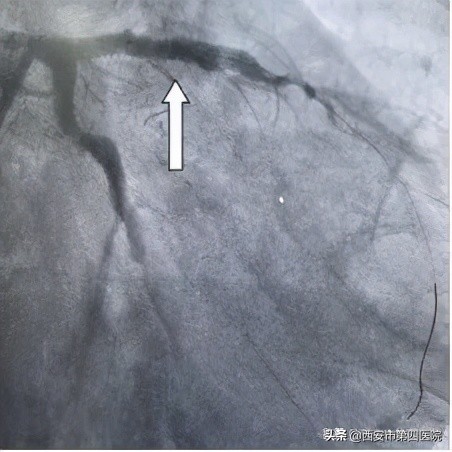

OCT显示前降支中段重度狭窄

OCT显示右冠狭窄处斑块破裂

经充分预扩张处理后,在OCT指引下均成功植入药物洗脱支架,随后球囊后扩张后OCT评价,支架完全贴壁,未见支架远近端夹层。